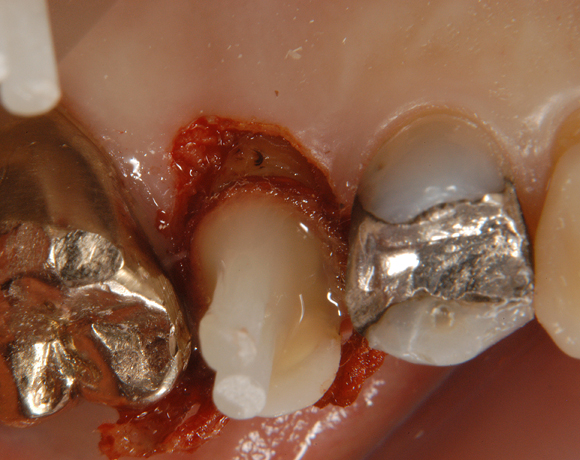

Ein Projekt aus dem Jahr 2003